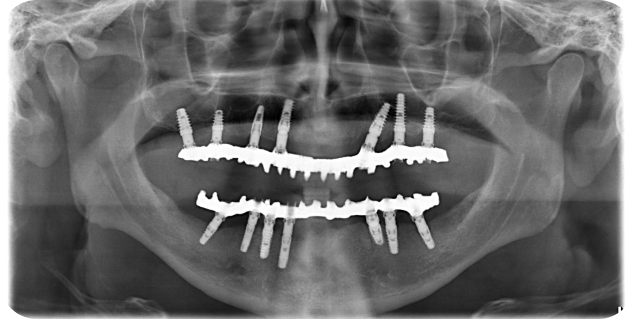

A 58-year-old black woman, referred by a prosthodontist, presented to the dental office.

A 58-year-old black woman, referred by a prosthodontist, presented to the dental office.

A 58-year-old black woman, referred by a prosthodontist, presented to the dental office.

A 58-year-old black woman, referred by a prosthodontist, presented to the dental office.